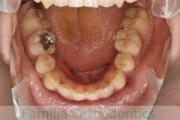

上顎

下顎

前歯の関係など

右側

正面

左側